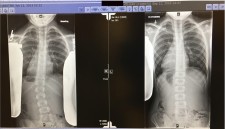

X-ray results

REACT, the only Physical Therapy center in the world that uses the patent-pending Reavy Method, has employed their proprietary treatment methods to correct the scoliosis of a then-10-year-old child (now 12 years old) from Chicago, a total of 16 degrees in 1.5 years with no assistance from a back brace or surgery. To date, this is the first recorded case of reversing scoliosis so drastically with the Reavy Method and is recognized by John F. Sarwark, MD, Head of Orthopaedic Surgery and Sports Medicine at Ann & Robert H. Lurie Children’s Hospital of Chicago, where Killian is treated.

Treating the child’s body as a whole allowed REACT to reverse her scoliosis in 1.5 years through their unique approach to physical therapy and a series of exercises performed at REACT, all without the use of an uncomfortable and unsightly brace or serious surgery. It is important to understand that every scoliosis case is different and parents and patients need to know surgery and braces are not the ONLY answers for success. With Killian's case, Physical Therapy was the answer for her impressive improvement.